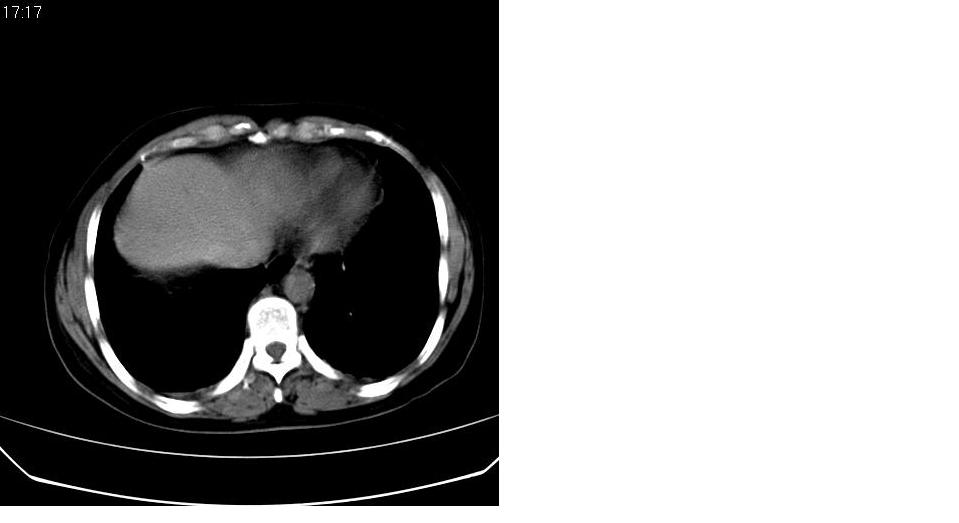

标题: CT16839:胸部CT平扫

女 50岁,在其他医院确诊肺癌.

都已发生广泛转移了,意义不大。

考虑 肺癌伴肺及纵隔转移,心包膜增厚